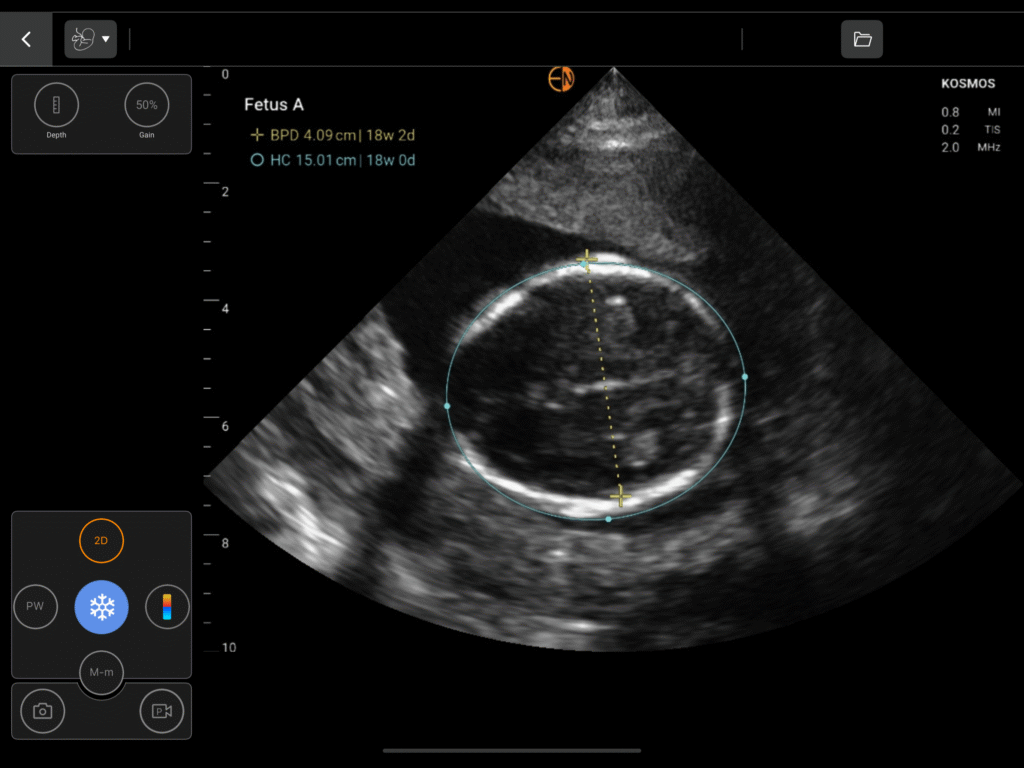

Comprehensive OB Biometry

A complete measurement and calculation package for all three trimesters, including Gestational Sac (GS), Crown Rump Length (CRL), Biparietal Diameter (BPD), Head Circumference (HC), Abdominal Circumference (AC), and Femur Length (FL).

OB/GYN Image Gallery